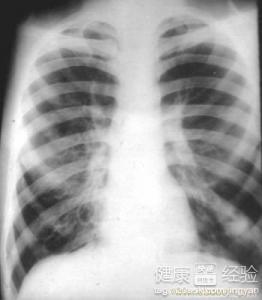

支氣管炎是一種常見(jiàn)的呼吸系統(tǒng)疾病,其癥狀包括咳嗽、咳痰、呼吸急促等,許多患者關(guān)心的問(wèn)題是:支氣管炎能自愈嗎?本文將詳細(xì)解析支氣管炎的類(lèi)型、癥狀、治療方法以及能否自愈的問(wèn)題,幫助患者更好地了解并應(yīng)對(duì)這一疾病。

支氣管炎是指氣管、支氣管黏膜及其周?chē)M織的炎癥,根據(jù)其發(fā)病的急緩,可分為急性支氣管炎和慢性支氣管炎,急性支氣管炎通常由于病毒、細(xì)菌等感染引起,癥狀明顯且病程較短;而慢性支氣管炎則由于長(zhǎng)期吸煙、空氣污染等因素導(dǎo)致,癥狀持續(xù)較長(zhǎng)時(shí)間,易反復(fù)發(fā)作。